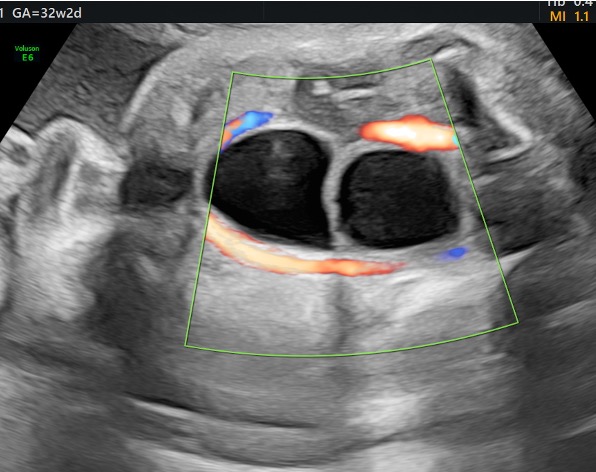

Caso 1 –

CASO CLINICO MAGGIO 25_zullino

Caso 2.

Caso del mese maggio 25